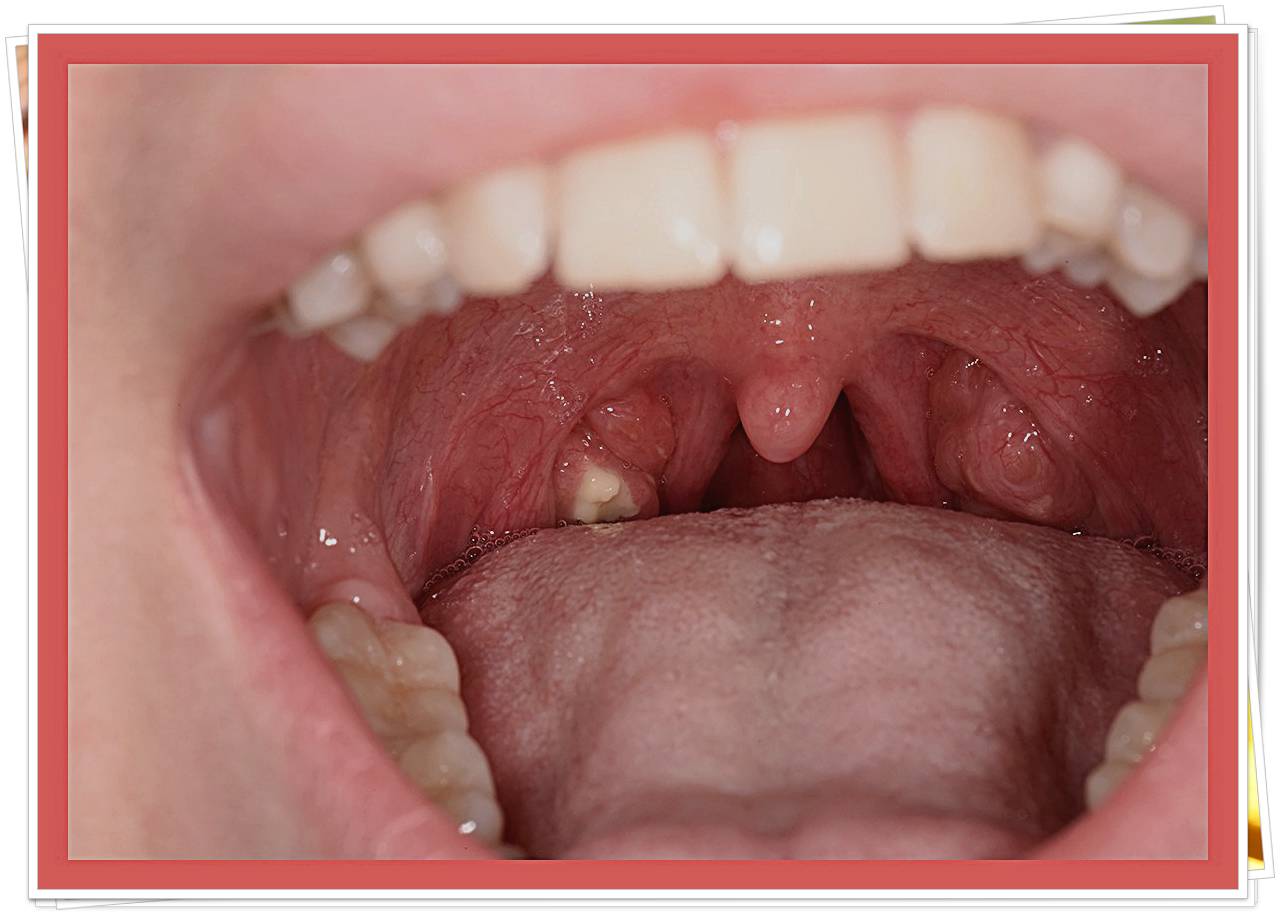

- 편도 부위의 흰색·노란색 알갱이

- 거울로 목 안쪽을 비춰봤을 때 작은 결석이 보인다.

- 목에서 특이한 냄새 덩어리 배출 경험

- 기침하거나 음식 먹다 작은 돌처럼 생긴 알갱이가 나온 적이 있다.